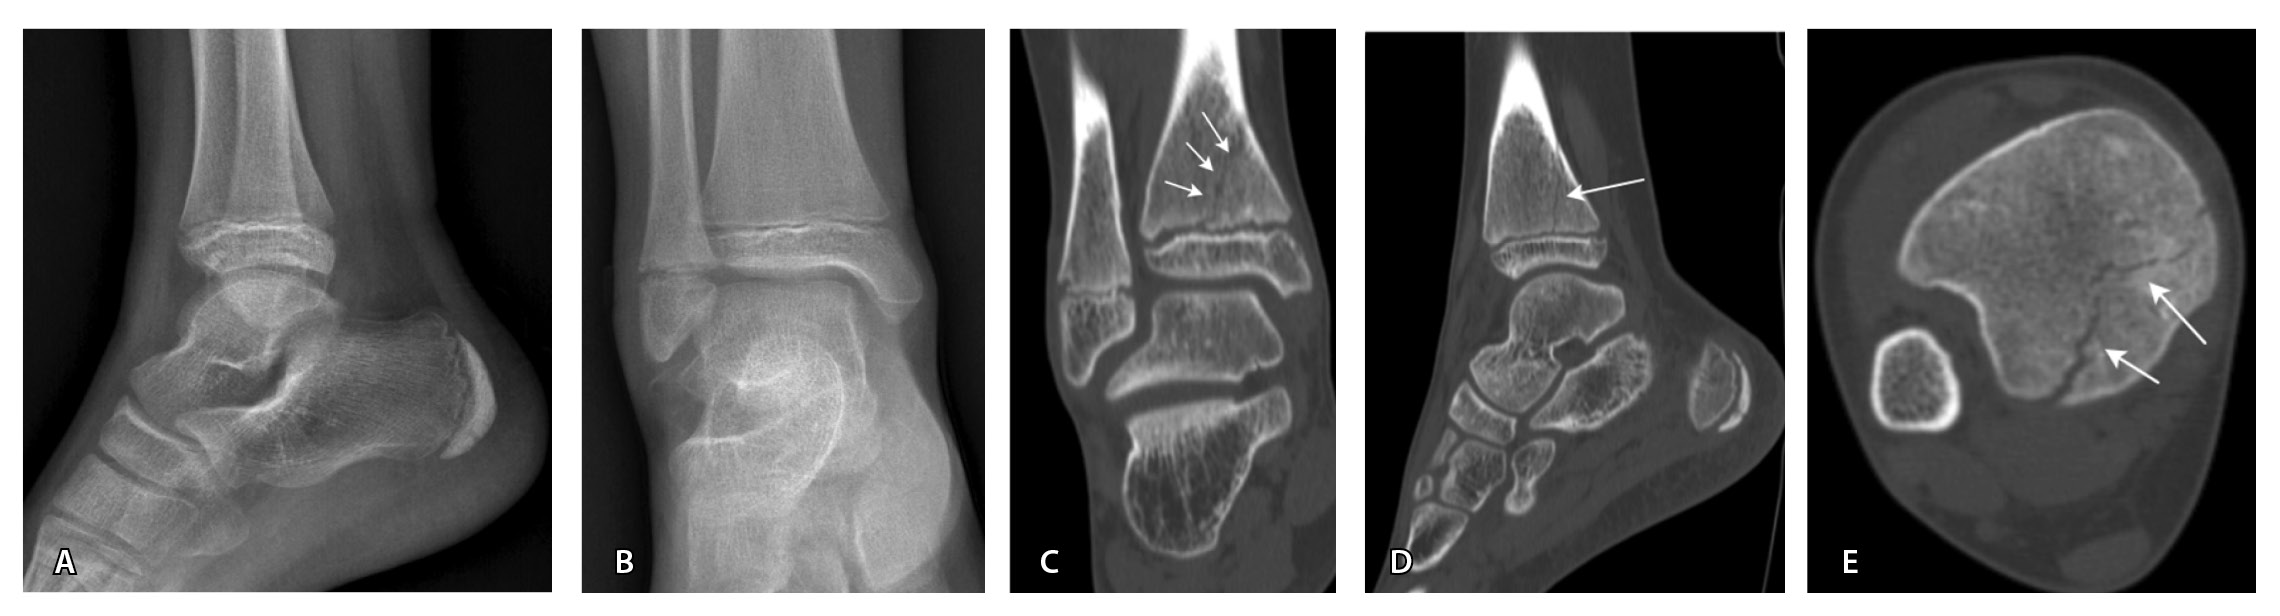

Переломы без смещения фрагментов, а также краевые и авульсионные переломы не всегда четко визуализируются на рентгенограммах из-за суперпозиции теней, наличия фиксирующих шин и гипсовых повязок, которые накладываются на зону интереса. При клинических признаках перелома и рентгеннегативной картине у таких пациентов КТ имеет большую диагностическую значимость (рис. 2).

Рис. 2. Рентгеннегативный перелом дистального метадиафиза большеберцовой кости 2-го типа по Солтеру – Харрису (стрелки) у мальчика 11 лет: А, Б – рентгенография; В – компьютерная томография (КТ), корональная плоскость; Г – КТ, сагиттальная плоскость; Д – КТ, аксиальная плоскость